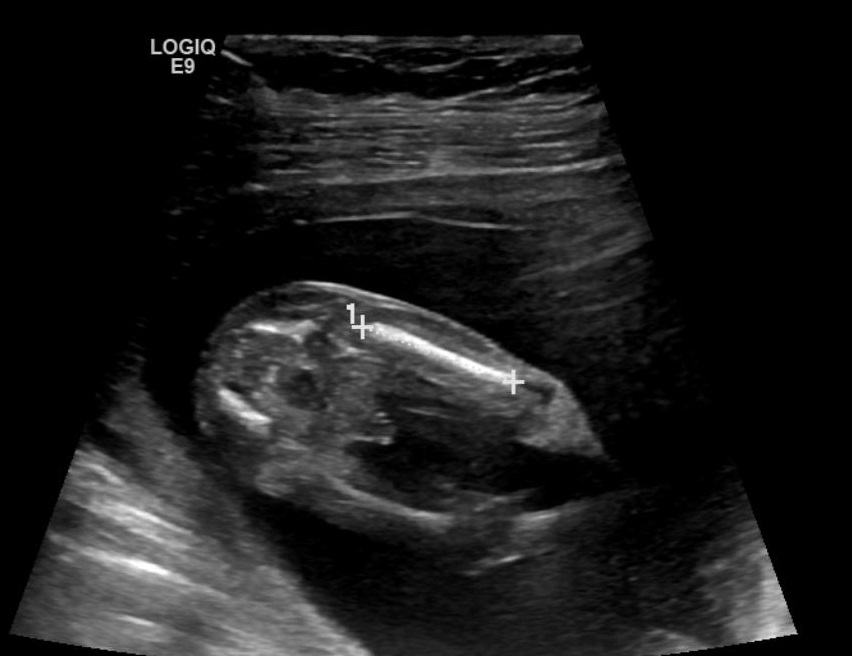

These all looks boy shots don't they, I'm in denial & clutching at straws here after trying for a girl ... Looks like 3 boys for us !

Forgot to mention measuring 15 weeks 3 days

Looks very boyish to me.

Yes, I hate to say it but it's looking very promising for another little boy.

That's a boy. I'm sorry you didn't hear pink.

It looks like a boy.